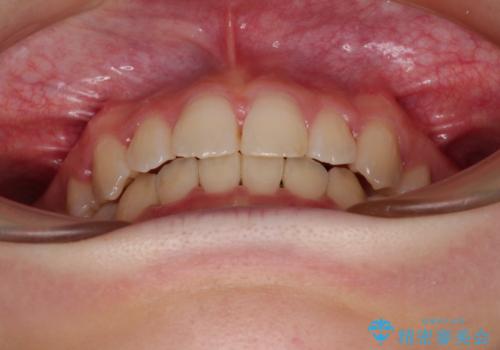

- 口元の閉じにくさを気にして来院された患者様です。

上下ともに歯列が前方に突出していたため、上下左右の第一小臼歯4本を抜去し、ワイヤー装置による矯正治療を行うこととしました。

上下左右4本抜歯する場合には、通常2年から2年半ほどの期間を要しますが、舌のトレーニングをしっかりと行っていただいたことで、1年9ヶ月で終了することができました。